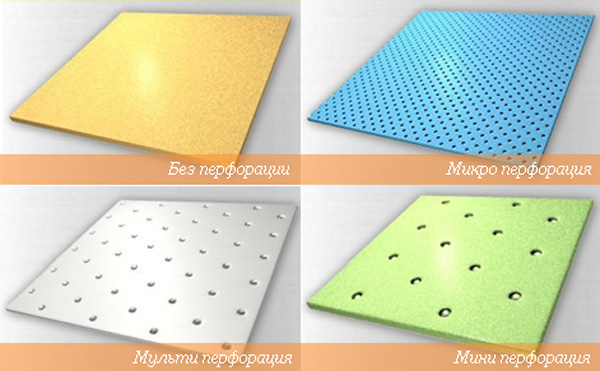

– великолепная вентиляция за счет многочисленных отверстий оптимальное время фиксации изделия (5—8 мин.);